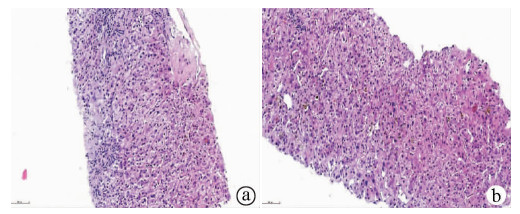

A case of splenic arteriovenous fistula with abdominal pain and gastrointestinal bleeding as the first symptoms

Yuanyuan CAI, Zhongwen WU, Juan LU

2021, 37(5): 1186-1188. DOI: 10.3969/j.issn.1001-5256.2021.05.043

Abstract(1011) HTML (291) PDF (2876KB)(49)

Abstract: